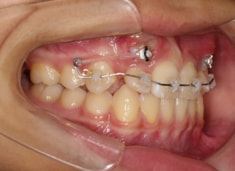

治療前

治療開始時